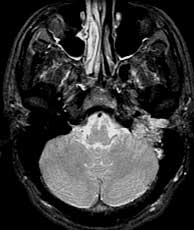

T2 SE axials

Findings: Mostly bright signal mass in the left medial skull base which abuts the basiocciput (basi) and invades the left external auditory canal (eac). The mass has several linear and curvilinear foci of decreased signal within.